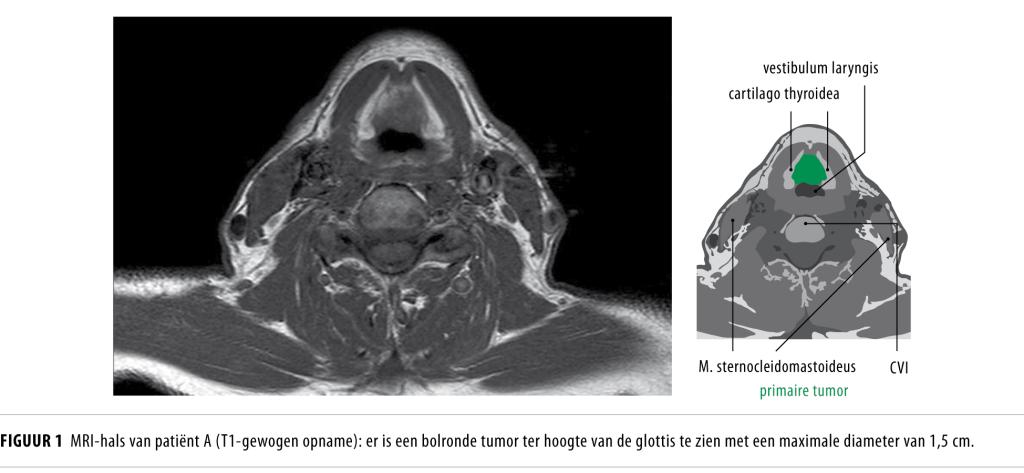

Een cysteuze zwelling in de hals bij volwassen patiënten is meestal een laterale halscyste, maar kan ook een lymfekliermetastase van een primaire tumor in het hoofd-halsgebied zijn. Oplettendheid is met name geboden bij patiënten ouder dan 40 jaar en met risicofactoren als nicotinegebruik en alcoholabusus. Een lymfekliermetastase moet worden uitgesloten voordat de afwijking abusievelijk als laterale halscyste wordt behandeld.

Het is bekend dat lymfekliermetastasen van plaveiselcelcarcinomen uitgaande van de mucosa van de ring van Waldeyer (nasofarynx, tonsillen, tongbasis) een cysteuze verandering kunnen ondergaan en kunnen imponeren als een laterale halscyste.1 De kans dat een cysteuze zwelling in de hals bij patiënten ouder dan 40 jaar berust op een metastase van een hoofd-halstumor is circa 25%.2 In de praktijk blijkt het onderscheid moeilijk.

Patiënt A, een 54-jarige man, werd door de huisarts verwezen naar een kno-arts in een niet-academisch ziekenhuis in verband met een langzaam…